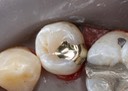

Joe Cha #18 pre-cementation

Joe Cha #18 finish